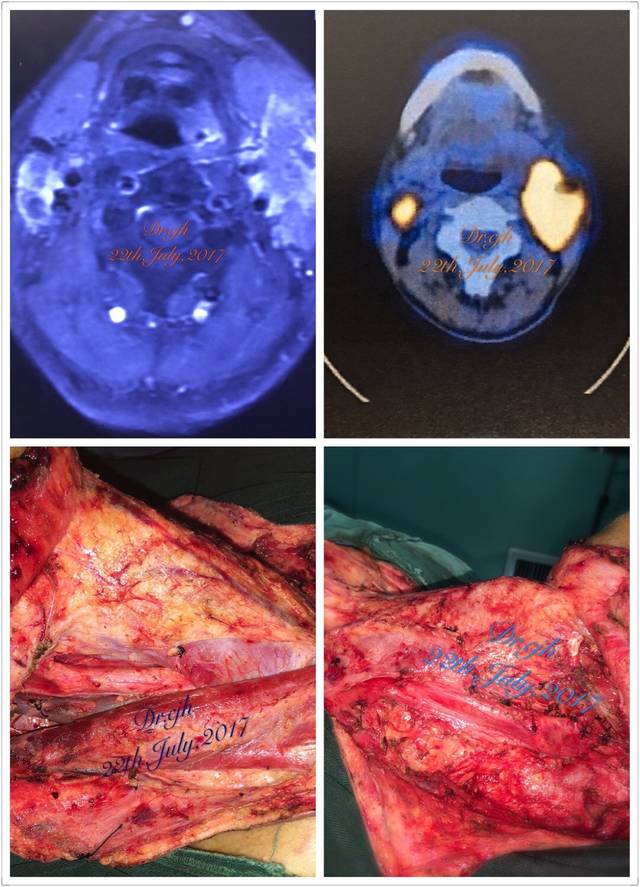

下咽癌切除颈部淋巴结234区清扫一例

图片尺寸960x1280

图片尺寸1280x960

下咽癌切除 颈部淋巴结2,3,4区清扫一例

图片尺寸640x480